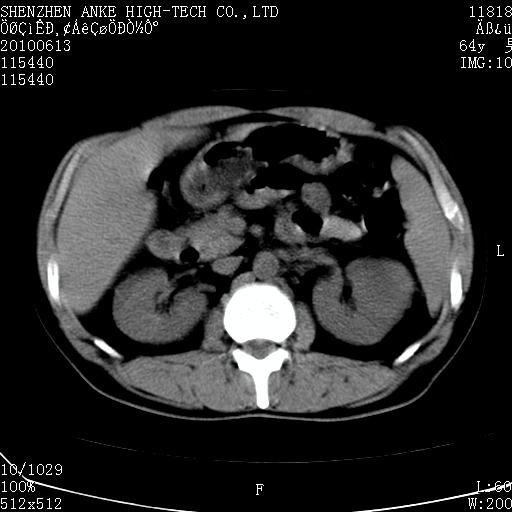

以下是引用beifangren在2010-7-26 22:05:00的发言:[br]左肾中极圆形占位,肾盏肾盂受压移位,建议增强。结合肺部结节。肝低密度灶,多为肾癌并肺部、肝转移。